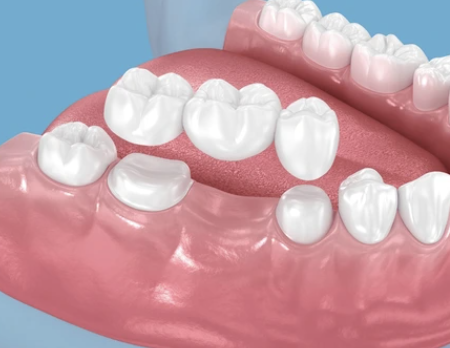

ブリッジ治療とは・・・

ブリッジ治療は、失ってしまった歯の両隣にある歯を「橋げた」にして、人工の歯を橋のように架ける治療法です。歯科用セメントでがっちりと固定するため、自分の歯に近い感覚でしっかり噛めるのが特徴です。